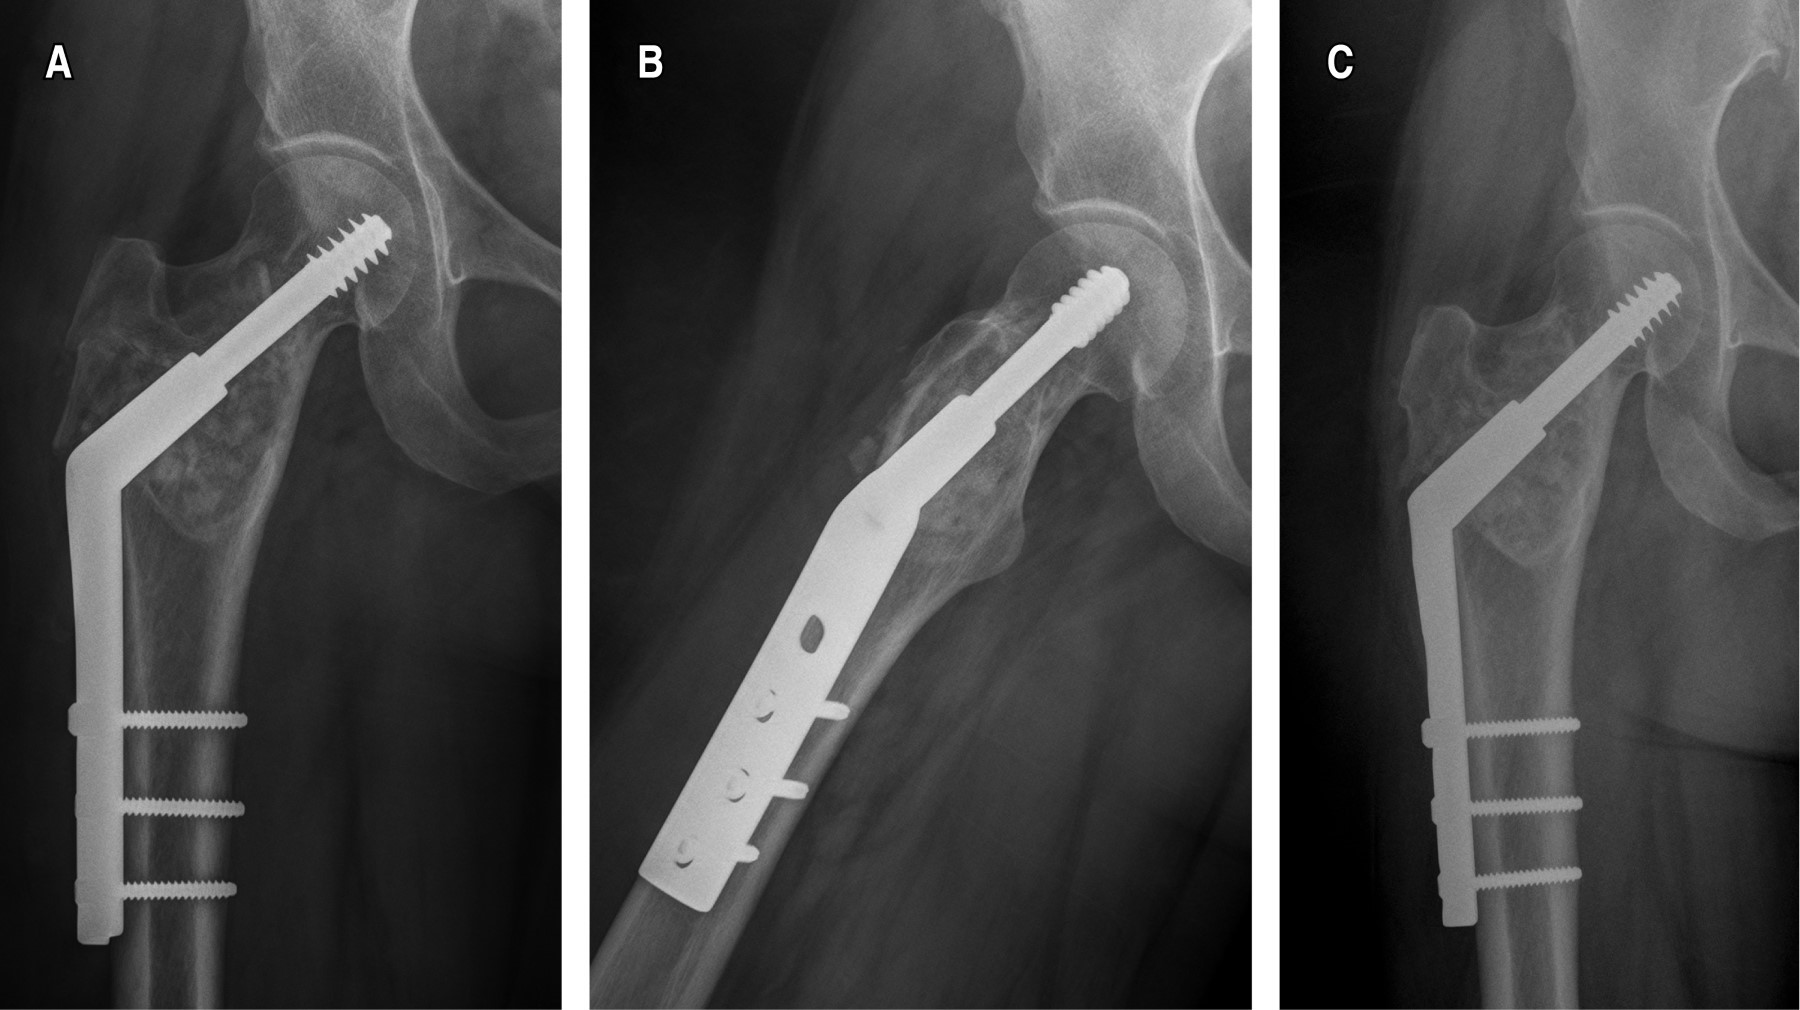

Figure 4